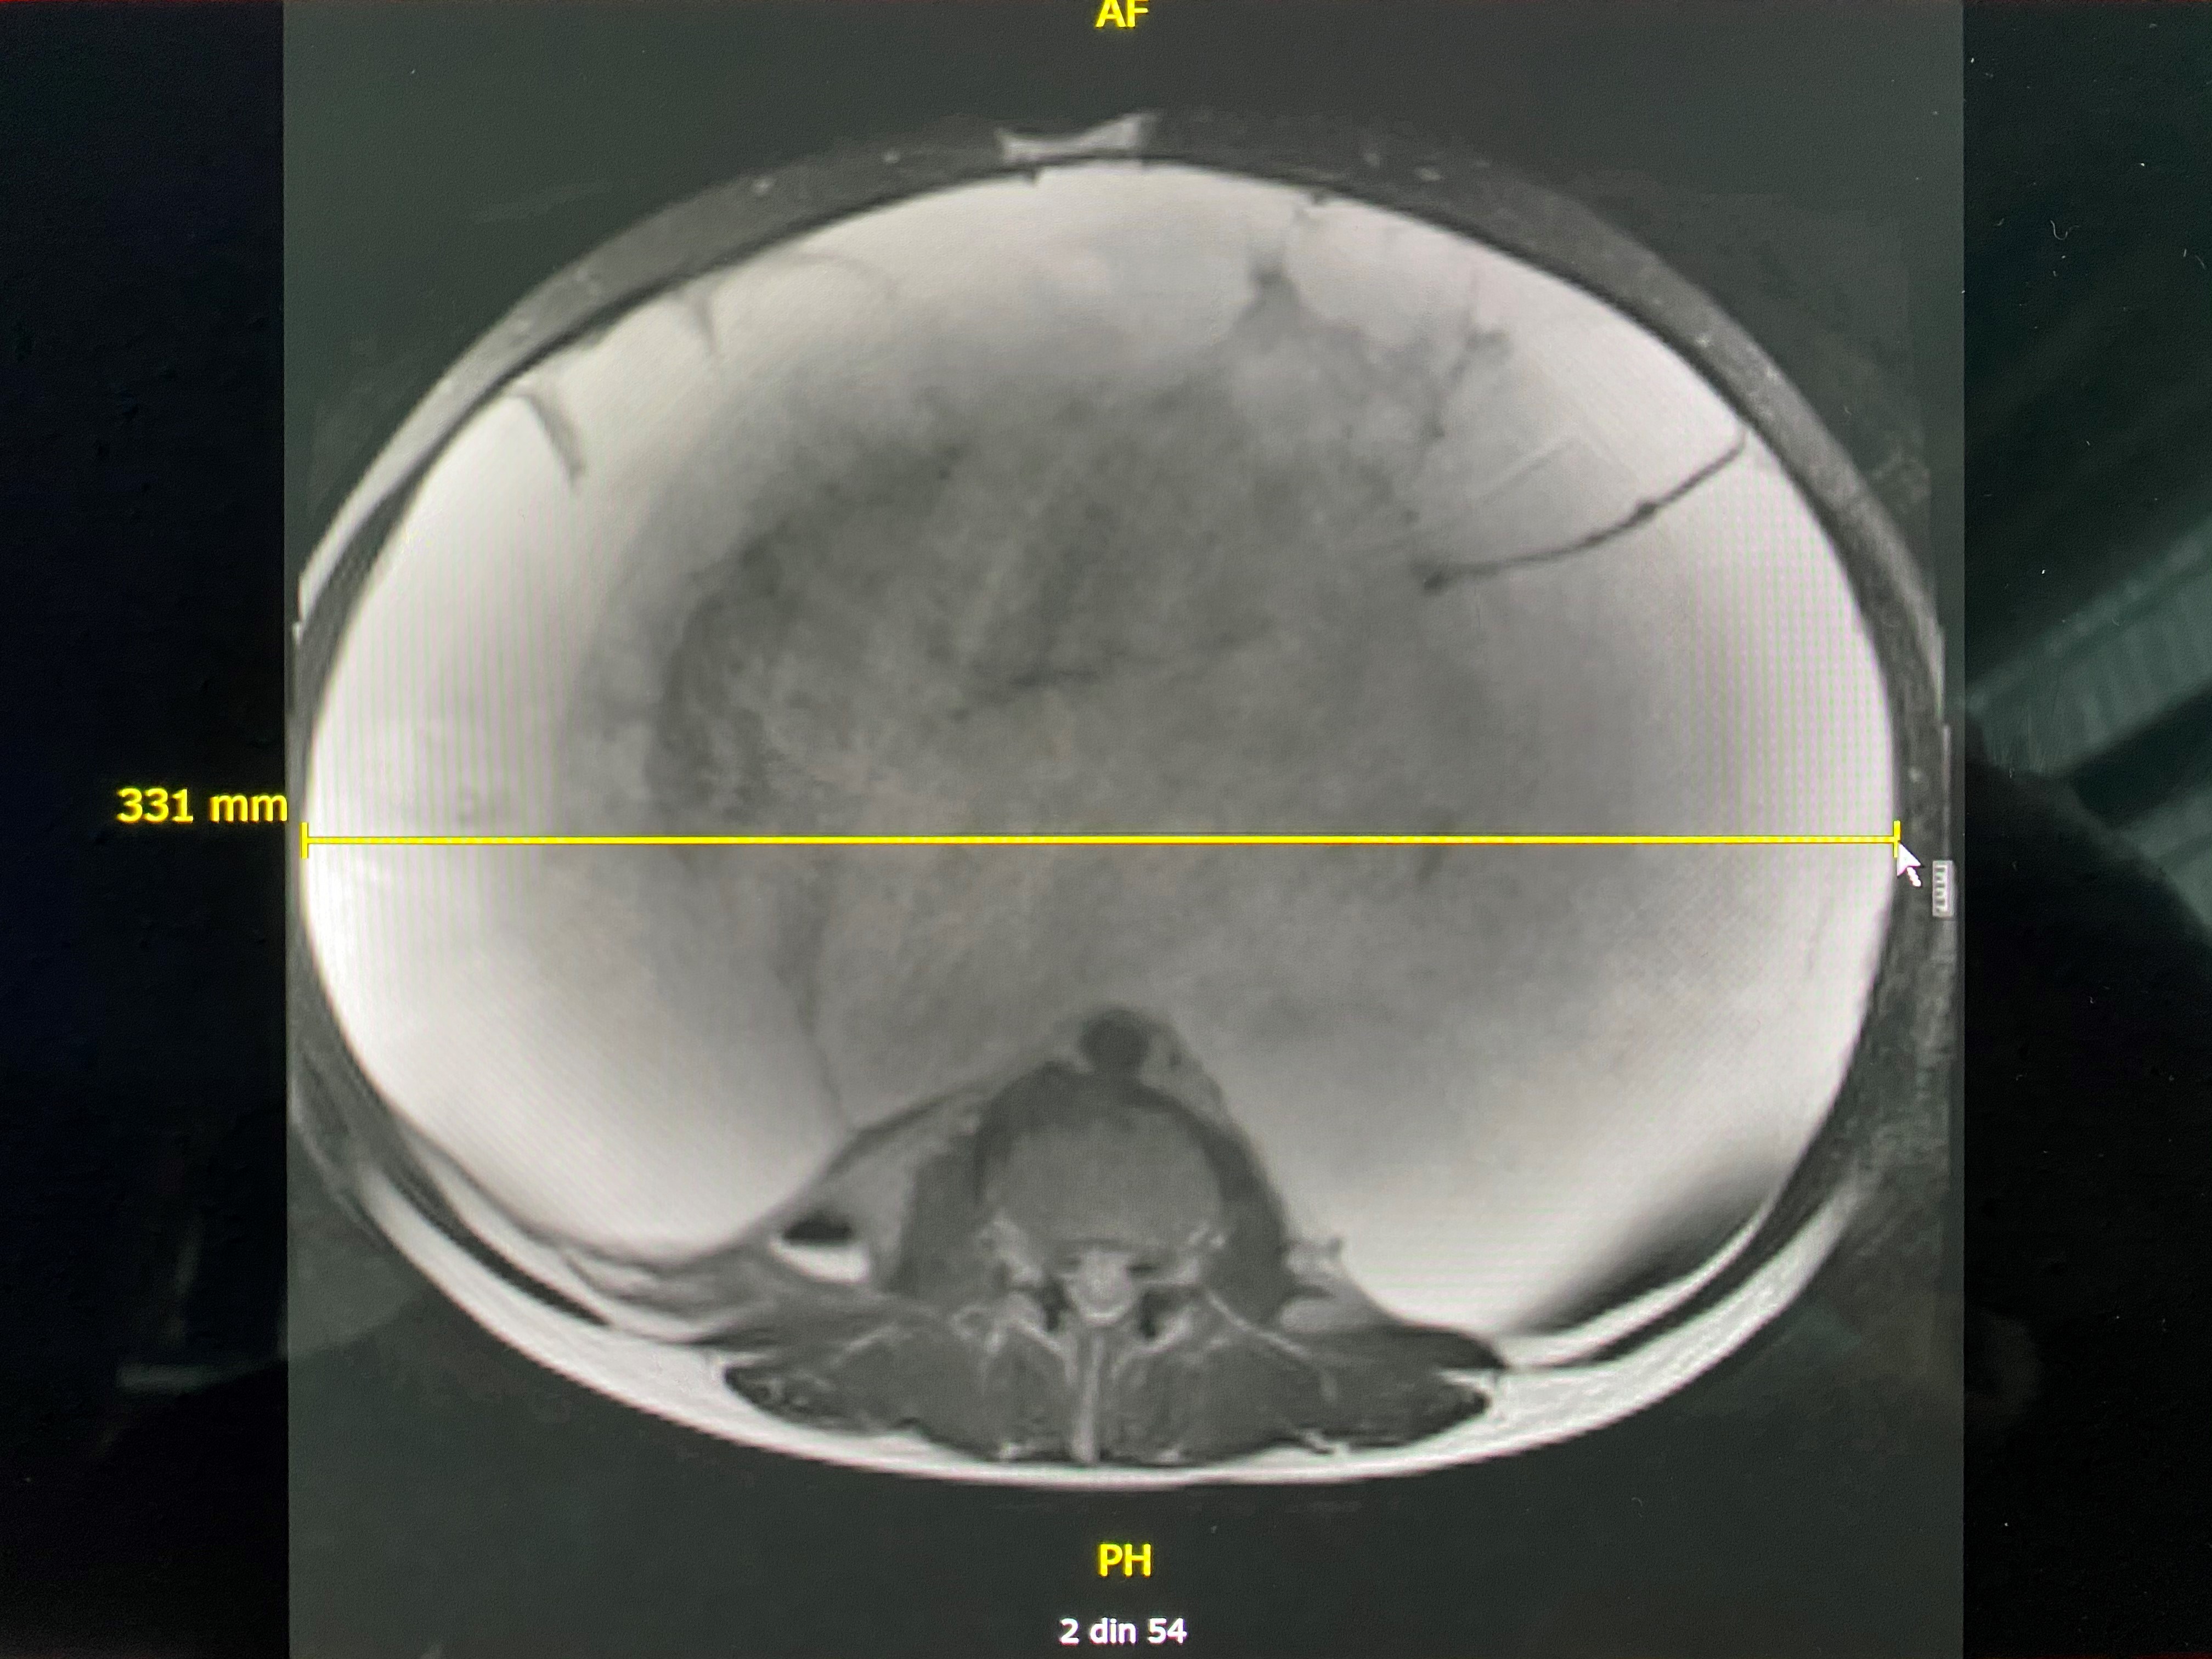

La examenul RMN se constata prezenta unei formatiuni tumorale abdominale chistice, de dimensiuni gigante. Avand un diametru orizontal de 33 de cm, tumora ocupa practic intreaga cavitate abdominala. Nu s-a putut stabili cu certitudine care a fost punctul de plecare si nici daca este vorba de o tumora benigna sau maligna.

Imagine RMN in plan orizontal